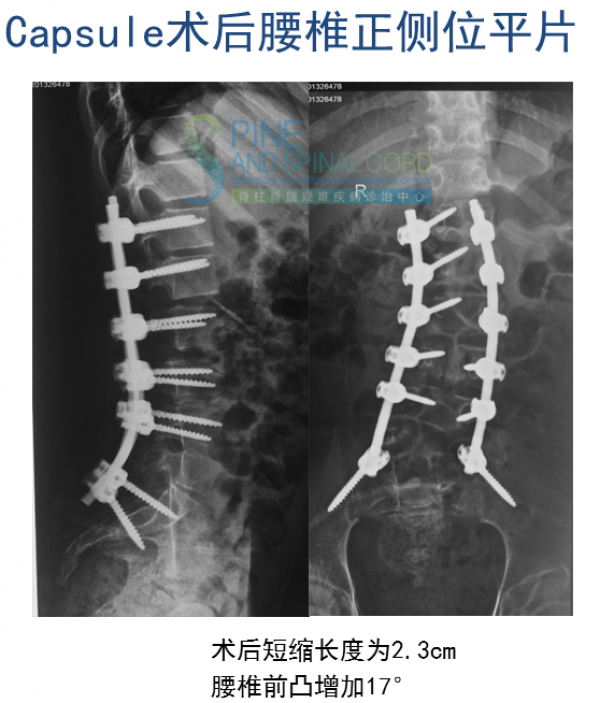

病例二 青少年型TCS

患者女,10岁,双下肢畸形伴尿失禁9年,加重1年

8年前曾行神经松解术,术后尿失禁症状加重

体检:双下肢肌萎缩,双侧马高弓足、鞍区感觉障碍,双下肢反射亢进,babinski征阳性

下肢电生理示L2-S2双侧腰骶神经根受累